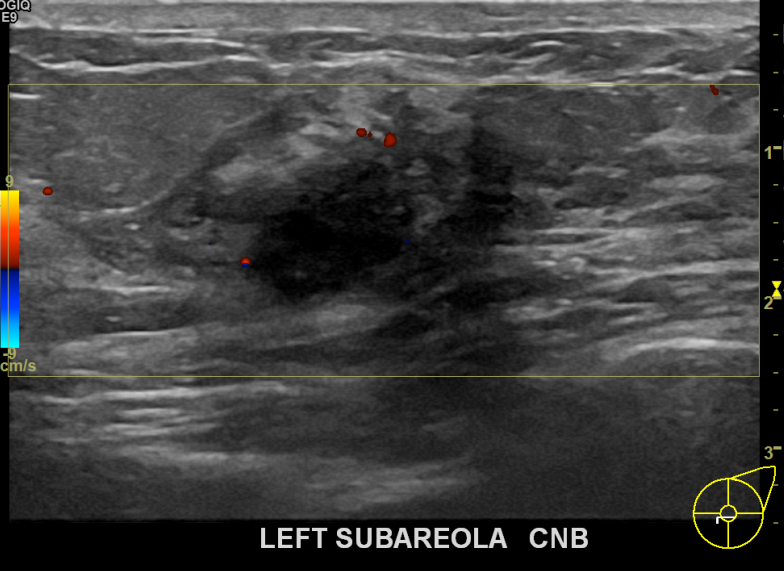

아산유외과개원후 739번째 유방암진단

상기환자 본원에서 꾸준히 추적관찰하던 40대 여성분으로 새롭게 생겨난 혹 있어 좌측유방멍울 조직검사시행후 유방암 진단되었습니다.